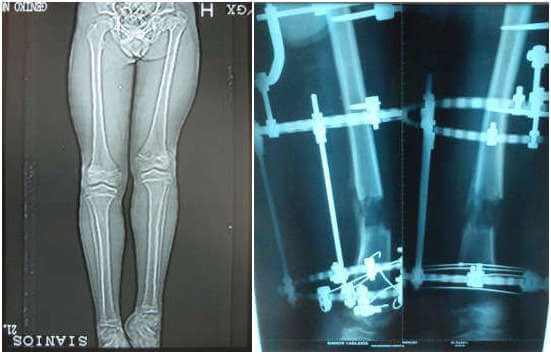

- Δυσπλασίες με μεγαλύτερες ανισοσκελίες, αντιμετωπίζονται με επιμήκυνση με διατατική ιστογένεση με την μέθοδο Ilizarov.